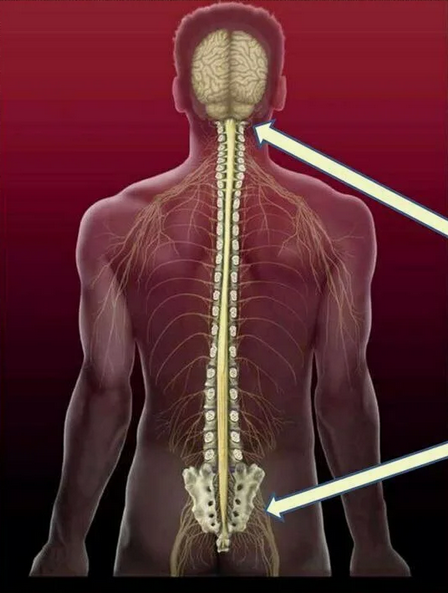

Магнитно-резонансная томография (МРТ):один из самых эффективных методов диагностики заболеваний

В случае перелома шейки бедра компания МосРентген Центр госпитализирует в Склиф для эндопротезирования.